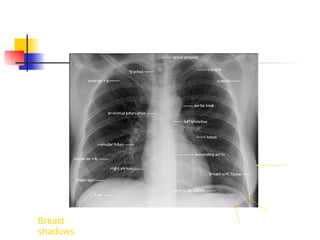

(1) aortic arch

(2) pulmonary trunk

(3) left atrial appendage

(4) left ventricle

(5) right atrium

(6) superior vena cava

(7 & 8) diaphragm

(9) transverse fissure

Lung Anatomy

(1) oblique fissure

(2) transverse fissure

(3) retrocardiac space

(4) retrosternal space

 Breast shadows

Breast

shadows